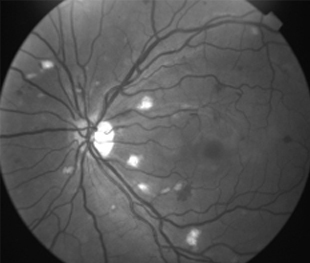

Mujer de 32 años con cefalea después de liposucción con anestesia general 10 días antes de consultar

AV: OD 0,15 OI 0,30 con corrección

IDX

Retinopatía de Purtcher Secundaria a Embolismo Graso después de Liposucción

2 meses: disminución de manchas algodonosas y hemorragias con mejoría de circulación

Funcional

OD - 0,50 esf 0,9 +2

OI -0,25 esf 1,00